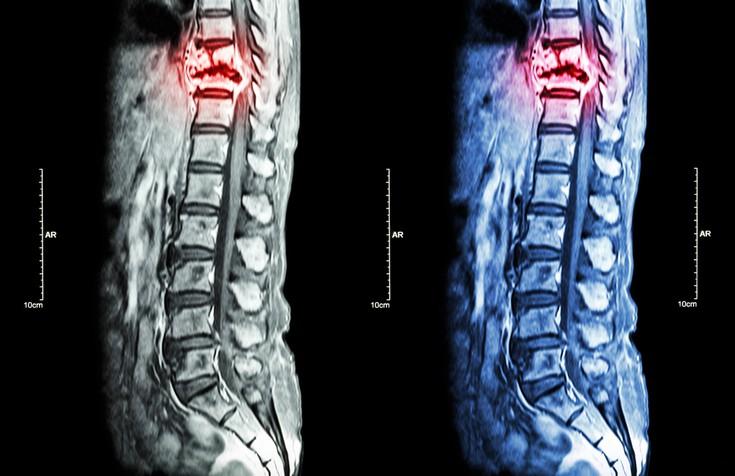

Metastasis tulang boleh didiagnosis menggunakan ujian gambar seperti:

- MRI;